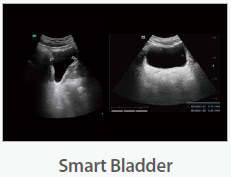

Mindray Ultrasound Consona N9